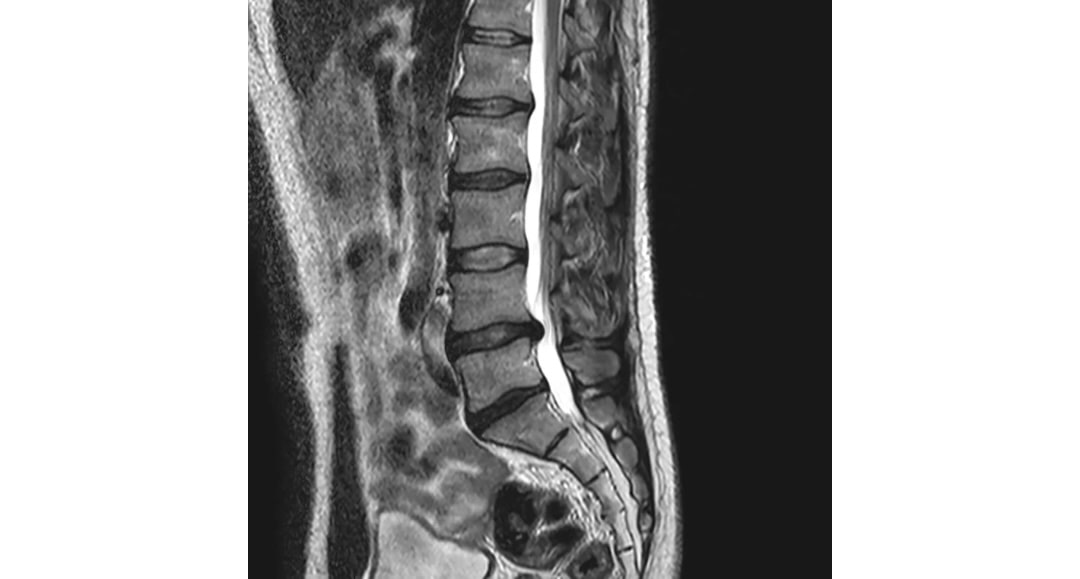

| 腰椎椎間板ヘルニア | 腰の骨と骨の間にある椎間板が飛び出し、坐骨神経を圧迫することで痛みやしびれを引き起こします。猫背や反り腰など、腰に負担のかかる座り方を長時間続けることで、椎間板への圧力が不均一になり、ヘルニアのリスクが高まります。 |

| 脊柱管狭窄症 | 背骨の中を通る神経の通り道(脊柱管)が狭くなり、坐骨神経を含む神経が圧迫されることで症状が現れます。姿勢の悪さや加齢による骨の変形が主な原因であり、座り方によっては腰への負担が増し、症状が悪化することがあります。 |

| 腰椎すべり症 | 腰の骨が前方にずれてしまう状態です。これにより神経が圧迫され、坐骨神経痛の症状が現れることがあります。悪い座り方や姿勢の崩れは腰椎への負担を増大させ、すべり症の発症や進行に影響を与える可能性があります。 |